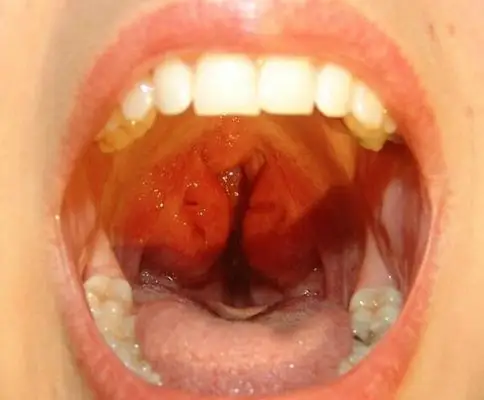

扁桃体发炎自愈要几天 嗓子咽唾沫疼像刀割一样

喉咙正常不发炎应该是什么样的,让我们一起看一看吧

扁桃体炎

喉咙发炎图片 (16)_有来医生

我的咽喉正常吗?